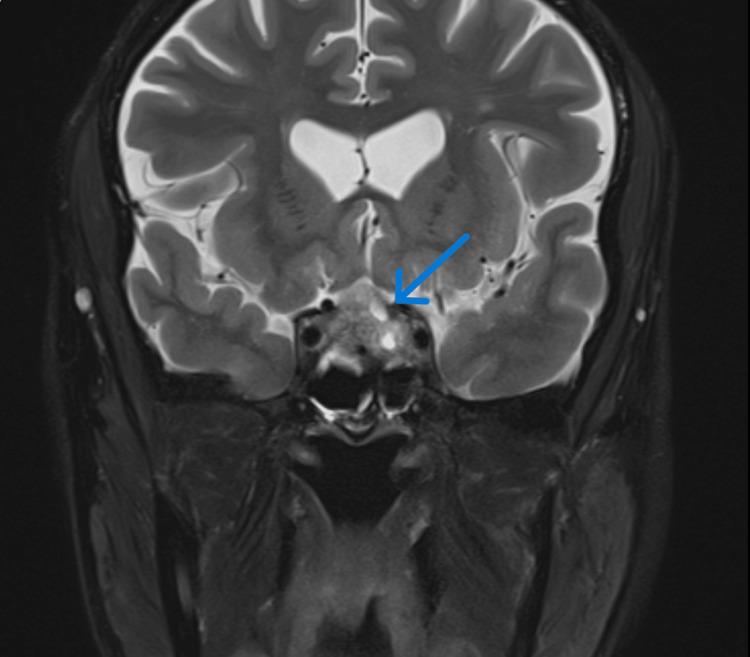

Pituitary apoplexy is a life-threatening condition caused by a rapid expansion of the pituitary tumor due to hemorrhage or infarction. It usually presents with acute onset severe headache and can also be associated with visual field defects and ophthalmoplegia. Similarly, ocular myasthenia gravis, which is an autoimmune condition causing muscle fatiguability, also presents with ophthalmoplegia, commonly ptosis and diplopia. A 53-year-old male patient with a past history of adrenal insufficiency presented with acute onset headache. On examination, he had bilateral asymmetrical partial ptosis and left-side medial rectus palsy with mild fatiguability. He had normal visual fields and sparing of the pupils. Acetylcholine receptor antibodies were positive but failed to demonstrate a decremental response in nerve conduction studies. The patient was started on neostigmine on clinical suspicion of ocular myasthenia gravis. A magnetic resonance imaging (MRI) scan of the brain was arranged to look for any intracranial pathology for persistent headache and it revealed evidence of pituitary apoplexy with compression of optic chiasm and partial obliteration of bilateral cavernous sinuses. In view of MRI findings, a diagnosis of pituitary apoplexy with third cranial nerve involvement was considered the first differential diagnosis, and the patient was started on replacement hormones while temporarily withholding neostigmine. Following multidisciplinary input, it was decided to manage the patient conservatively. A repeat MRI brain was planned to assess the evolution which revealed resolution of pituitary apoplexy. Despite this, the patient continued to have ophthalmoplegia and fatigable partial ptosis. Pyridostigmine was restarted following which the patient fully recovered, confirming the diagnosis of ocular myasthenia gravis presenting concomitantly with pituitary apoplexy.

垂体卒中是一种由垂体肿瘤因出血或梗死而迅速扩大所导致的危及生命的病症。它通常急性起病,表现为严重头痛,还可能伴有视野缺损和眼肌麻痹。同样,眼肌型重症肌无力是一种导致肌肉易疲劳的自身免疫性疾病,也表现为眼肌麻痹,常见上睑下垂和复视。一名有肾上腺功能不全病史的53岁男性患者出现急性头痛。检查发现,他有双侧不对称性部分上睑下垂和左侧内直肌麻痹,伴有轻度易疲劳性。他视野正常,瞳孔未受累。乙酰胆碱受体抗体呈阳性,但神经传导研究未显示递减反应。临床怀疑为眼肌型重症肌无力,遂开始给予患者新斯的明治疗。安排了脑部磁共振成像(MRI)扫描以查找持续性头痛的任何颅内病变,结果显示有垂体卒中的证据,视交叉受压,双侧海绵窦部分闭塞。鉴于MRI检查结果,首先考虑诊断为累及第三脑神经的垂体卒中,开始给予患者补充激素,同时暂时停用新斯的明。经过多学科会诊后,决定对患者进行保守治疗。计划再次进行脑部MRI检查以评估病情演变,结果显示垂体卒中已消退。尽管如此,患者仍有眼肌麻痹和可疲劳性部分上睑下垂。重新开始给予吡啶斯的明治疗后,患者完全康复,证实诊断为眼肌型重症肌无力与垂体卒中同时存在。